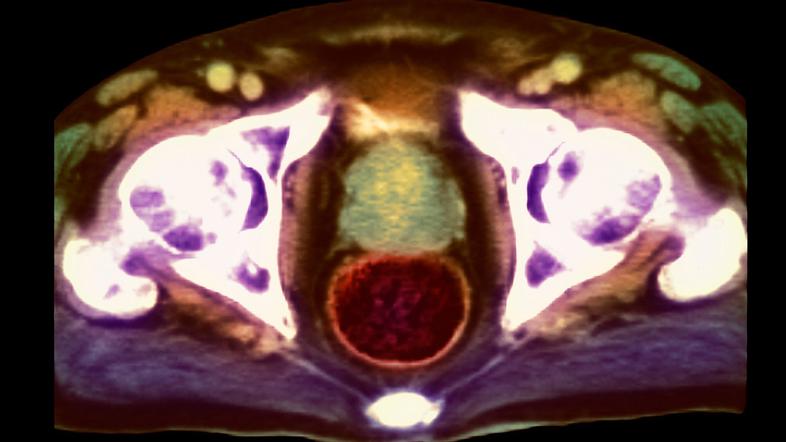

Rak prostate

Na evropski ravni sta v pripravi  dva tovrstna programa, za raka pljuč in raka prostate, ki bosta v prihodnje prav tako lahko pripomogla k rešitvi številnih življenj. V Državnem svetu so včeraj pripravili posvet o možnosti uvedbe organiziranega presejalnega programa za zgodnje odkrivanje raka prostate na državni ravniRak prostate je ena najpogostejših vrst raka pri moških, za katerim zboli vsak četrti moški po 50. letu starosti.

V Sloveniji po podatkih državnega Registra raka na Onkološkem inštitutu Ljubljana vsako leto za rakom prostate zboli okoli 1600 moških, umre pa okoli 440. V letu 2019 je za rakom prostate zbolelo 1565 moških, umrlo pa 445. Ob koncu leta 2019 je med nami živelo 15.922 bolnikov, ki jim je bila kdaj v življenju postavljena diagnoza raka prostate. Skoraj tri četrtine bolnikov je starejših od 60 let..

Praviloma raste zelo počasi, od nastanka bolezni do kliničnih znakov mine 9-17 let, do pojava oddaljenih zasevkov pa nadaljnjih 5-7 let. Petletno preživetje bolnikov z rakom prostate je dobro in je več kot 90-odstotno.